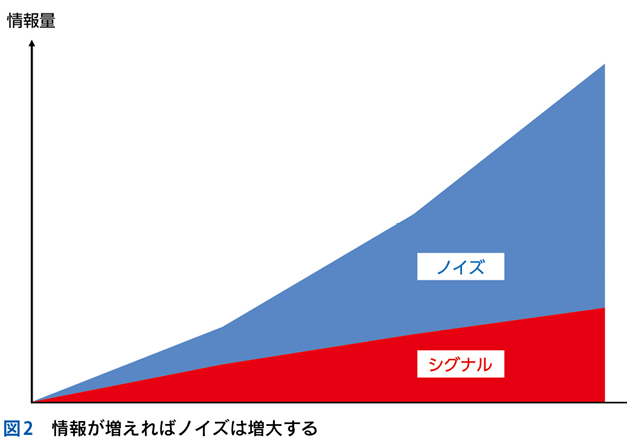

5 ノイズと多元論

▶ 「ノイズ」は,筆者的には臨床推論においてきわめて重要な概念であるため,第4章で詳述するが,フレーミングに関わるのでここで簡単に紹介しよう。ここでは「ノイズ」を,「患者の持つ情報のうち診断と直接的には関連しないもの」を指す語として使用する。対義語(診断と関連する情報)は「シグナル」である。星座のたとえで言えば「シグナル」は星座を構成する星,「ノイズ」は星座を構成しないが近傍にある「くず星」を指す(図4)。

▶ くず星とひとまとめに呼んでしまったが,厳密に言えばノイズには質的に「偽陽性情報」と「多元論で説明される情報」の2種類がある。前者は器質的疾患のシグナルではない情報であり,診断と無関係な疫学的情報,器質因のない症状,検査データのランダムなゆらぎといった,純粋に「ジャンク」な情報である。後者は併存する他疾患や合併症に起因して発せられる情報である。後者は目的としている疾患の診断という点ではノイズだが,それ自体は別の疾患により説明が可能(別疾患のシグナル)であるため,対処不要というわけではない。このような相違はあるものの,どちらもその情報を含めた一元論で状況を解釈しようとすると診断を誤るため,本書ではまとめて「ノイズ」と呼ぶ。

▶ 学会における症例報告や医学雑誌に掲載されるケースレポートは,診断が判明した後(何がノイズで何がシグナルだったか判明した後)に作成されるため,ノイズは削除され,シグナルだけが提示されることが多い。聴衆や読者は提示される情報のすべてが診断に関与する(「意味のある」情報である)ことを期待し思考できる。しかし実際の患者は“ノイズまみれ”であり,臨床現場ではノイズとシグナルを前向きに見わける努力をしながら進まなければならない。

▶ ノイズの問題点は,当然のことだが診断を誤った方向に導くことにある。ノイズ情報を含めてフレーミングを行えば(すなわち,ノイズ情報も一元的に説明できるような疾患を探すことにすれば),ノイズの定義からしてフレーム内に真の診断が存在しなくなる。したがって,フレーミングに用いる問題定義からは,ノイズを慎重に排除する必要がある。

▶ ノイズとシグナルを診断前に完全に見わけることは不可能なので,安全なのは一元論(いわゆる「オッカムの剃刀」)に過度にこだわらず,「ノイズであることが否定できない(シグナルであることが確実でない)情報はフレーミングに用いない」あるいは「ノイズであることが否定できない情報を外したバージョンのフレーミングも用意する」という謙虚な態度をとることだろう。

▶ ノイズの可能性がある情報も含めた「全体像」から診断を導くのは直観に任せておいて,分析的診断におけるフレーミングの段階では,早期閉鎖を避けるため,確実にシグナルである少数の情報を軸にしていくべきである。ノイズの可能性がある情報についてはまずは多元論を許容して別個に解釈を行い,結果として一元論に統合されることがある,という接し方がよいだろう。